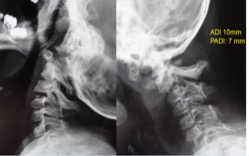

Instrumentación cervical en pacientes menores de 10 años. [Cervical Instrumentation and Fusion in Children Under 10 Years Old.]